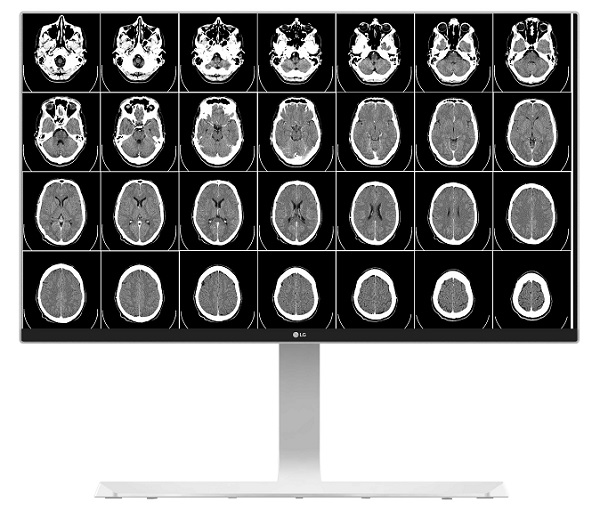

La firma acaba de anunciar que sus nuevos monitores 4K formarán parte de la maquinaria del sector en España. Gracias a estos equipos se han convertido en proveedores en el ámbito sanitario. Son monitores que ofrecen una elevada resolución, con lo que se convierten en herramientas muy útiles para los profesionales de la salud.

Pero, ¿de qué manera pueden resolver estas soluciones los problemas y el día a día de los entornos sanitarios? Pues bien, además de mejorar el trabajo diario de profesionales médicos y del ámbito de la enfermería, los monitores 4K de LG ofrecen a los pacientes la garantía de que en el ámbito hospitalario se están usando equipos de calidad.

De hecho, estos monitores no solo se emplean en consultas. Sino que están especialmente diseñados para ser usados en el ámbito quirúrgico, entorno que exige la máxima eficiencia y tecnología. En este caso, a través de imágenes de altísima resolución, para colaborar en las labores de diagnóstico.

Monitores 4K equipados para el entorno médico

La compañía surcoreana ha llegado ahora a un acuerdo con el Centro Endoscópico de la Mujer en Madrid para proporcionarles la tecnología multimedia más avanzada. Estos monitores con resolución 4K funcionan a través de la tecnología IPS, para mejorar la calidad de la imagen.

Para ofrecer la máxima calidad en las imágenes, los monitores están calibrados de manera rigurosa con un sistema de estabilización de luz de fondo. De este modo, los niveles de luminancia se mantienen estables. Y pueden adaptarse a la iluminación de los quirófanos, cuyaes condiciones son rigurosas y especiales.